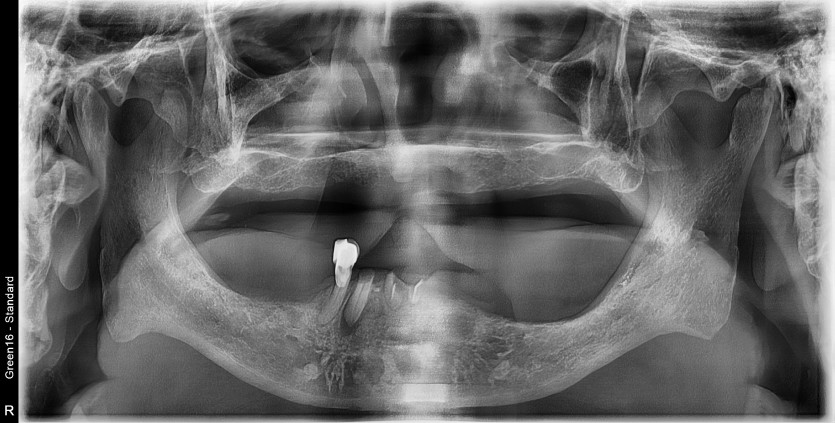

만 78세 전체 풀아치 증례

전체 풀아치 증례입니다.

12개 임플란트로 완성하였습니다.